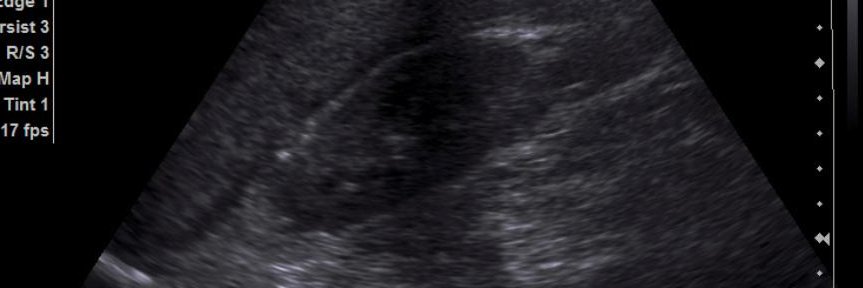

Why Your ESP Block Fails (And How To Fix It)